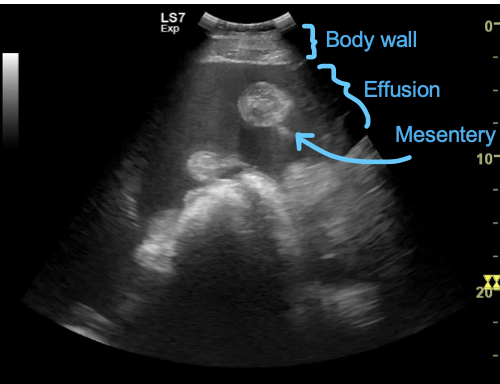

what does this peritoneal US show?

tadpole looking structure = intestine, normal to see the round part, but wouldnt usually see the mesentery (tail of tadpole)